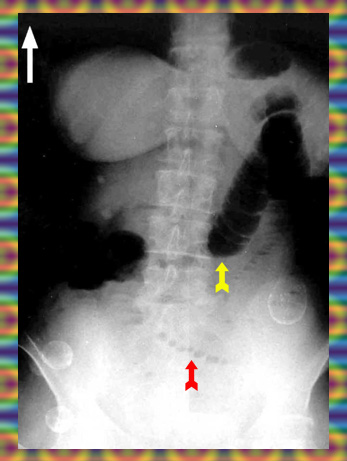

בצילום בטן סקירה ניתן לראות חסימות דינמיות, התרחבות של המעי הדק (תצלום 1.4), ופלסי אוויר נוזל במרכז הבטן המסודרים בצורת מדרגות (תצלום 2.4). הוולבולה קוניובנטס מודגשים לרוחב הרירית (תצלום 3.4).

בחסימות של המעי הדק לא תהיה עדות לאוויר בכרכשת (תצלום 4.4 - 5.4). בצילום צדדי של החלחולת לא ניתן לראות אוויר בחלחולת. לעומת זאת, בחסימות של הכרכשת יש הרחבה של הכרכשת והדגשה של ההאוסטרות בהיקף הבטן. בחולים שאובחנה בהם חסימה של הכרכשת, שבהם מסתם אילאוצקלי בלתי פעיל, תיראה הרחבה של הכרכשת והמעי הדק.